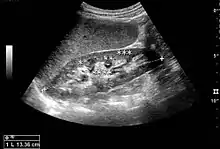

The kidney is divided into parenchyma and renal sinus. The renal sinus is hyperechoic and is composed of calyces, the renal pelvis, fat and the major intrarenal vessels. In the normal kidney, the urinary collecting system in the renal sinus is not visible, but it creates a heteroechoic appearance with the interposed fat and vessels. The parenchyma is more hypoechoic and homogenous and is divided into the outermost cortex and the innermost and slightly less echogenic medullary pyramids. Between the pyramids are the cortical infoldings, called columns of Bertin (Figure 1). In the pediatric patient, it is easier to differentiate the hypoechoic medullar pyramids from the more echogenic peripheral zone of the cortex in the parenchyma rim, as well as the columns of Bertin (Figure 2).[1]

Figure 1. Normal adult kidney. Measurement of kidney length on the US image is illustrated by ‘+’ and a dashed line. *Column of Bertin; ** pyramid; *** cortex; **** sinus.[1]